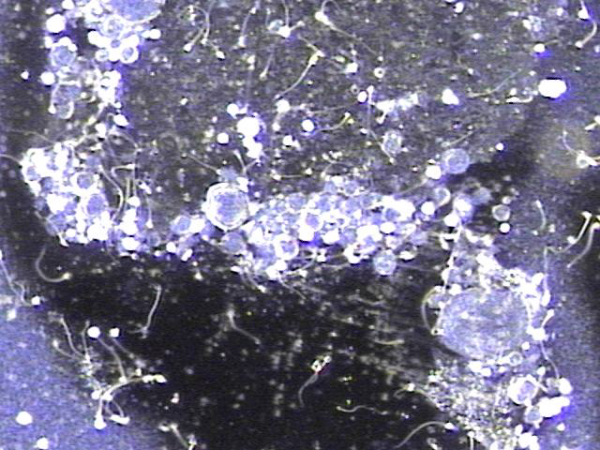

주2 ~3회 서울가정의학과에서 전립선과 사정관, 정관 그리고 정낭등의 표적 치료후 수명을 다하고 탈락되어 정관과 사정관 그리고 전립선관 등에 막혀 있던 탈락된 상피세포와 치료된 혈정액의 현미경학적 사진입니다.

This is a microscopic image of detached epithelial cell clusters and treated hematospermia that were discharged following targeted treatment of the prostate, ejaculatory duct, vas deferens, and seminal vesicles, performed 2 to 3 times per week at Seoul Family Medicine Clinic. These epithelial cells had reached the end of their life cycle and were obstructing the vas deferens, ejaculatory duct, and prostatic ducts prior to treatment.